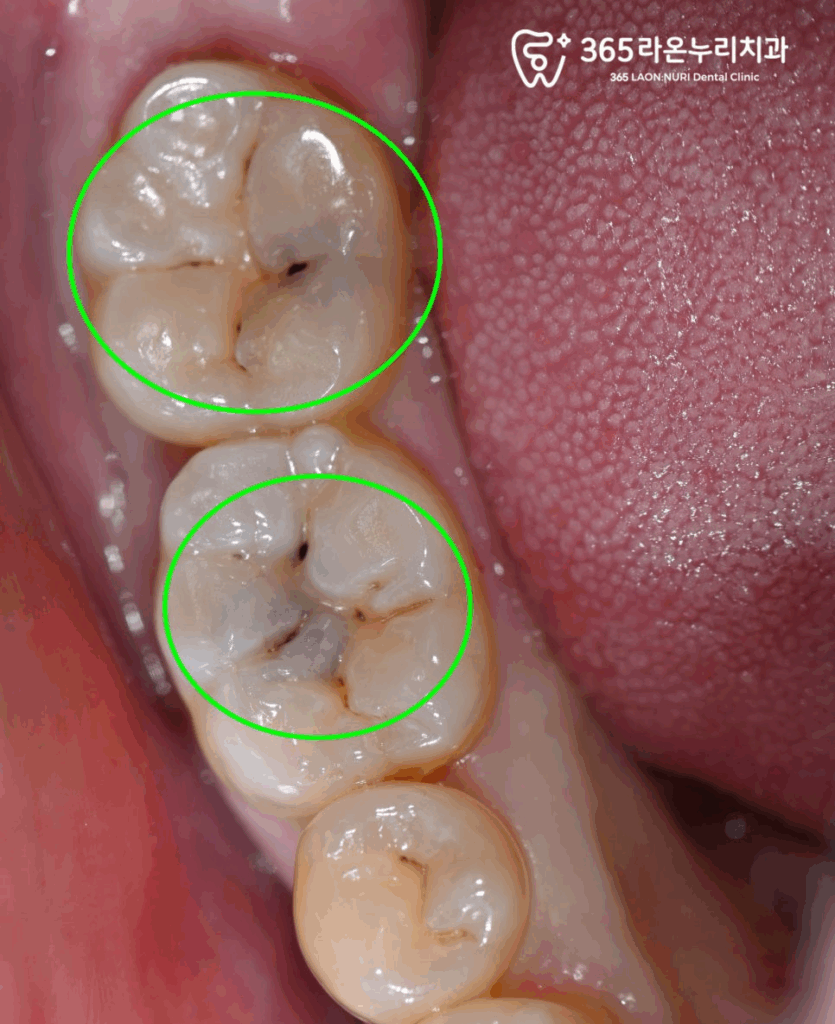

그리고 아래 어금니 교합면쪽에

진행된 우식증(충치)을 깔끔하게

없앨 필요가 있다고 진단을 내렸는데요.

구강 검진 이후,

내부로 깊이 진행될 우려가 있는

충치들을 깔끔하게

제거해드렸습니다.

어금니의 우식 범위가 크고

깊기 때문에 인레이 치료가 필요합니다.